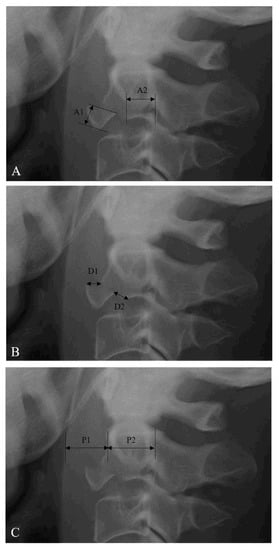

The avulsion fracture ratio of anterior C2 TD fractures was measured from lateral X-ray images (Figure 1A) [9]. The sagittal diameter of the inferior C2 endplate includes A1 and A2 (inferior endplate diameter of C2 TD fragment (A1) and remaining C2 body (A2)). The avulsion fracture ratio of anterior C2 TD fractures was defined as A1/(A1 + A2) × 100%. The fracture displacement of anterior C2 TD fractures was measured from lateral X-ray (Figure 1B) [7,8,9]. The displacement of the anterior C2 TD fragment was measured at the superior point (D1) and the posteroinferior point (D2). The fracture displacement of anterior C2 TD fractures was defined as (D1 + D2)/2. The prevertebral soft tissue thickness (PSVT) was measured from lateral X-ray (Figure 1C) [15]. The sagittal diameter of PSVT (P1) and the C2 body (P2) was measured at the C2 body midpoint. The ratio of PSVT was defined as P1/P2. The severity of PSVT at C2 was classified on a scale of grade 1 (mild, <0.4), grade 2 (moderate, 0.4–0.7), and grade 3 (severe, >0.7). The characteristics of the anterior C2 TD fractures, including associated C2 injury, associated C1 injury, associated C3–7 or thoracolumbar injuries, and neurologic status, were investigated. Clinical outcomes were evaluated using Odom’s criteria [16] and the visual analog scale (VAS) for neck pain [17]. All radiographic data were examined independently by two spine surgeons. Each independent observer checked the avulsion fracture ratio, fracture displacement, and severity of PSVT twice, and the average of the four measurements was used as the final result.

Figure 1. (A) The method of measuring the avulsion fracture ratio of anterior C2 (2nd cervical vertebra) tear drop (TD) fractures. The sagittal diameter of the inferior C2 endplate includes A1 and A2 (inferior endplate diameter of C2 TD fragment (A1) and remaining C2 body (A2)). Avulsion ratio of anterior C2 TD fracture = A1/(A1 + A2) × 100%. (B) The method of measuring the fracture displacement of anterior C2 TD fractures. The displacement of the fragment is measured at the superior point (D1) and the posteroinferior point (D2). Fracture displacement of anterior C2 TD fracture = (D1 + D2)/2. (C) The method of measuring the prevertebral soft tissue thickness (PSVT). The sagittal diameter of PSVT (P1) and C2 body (P2) is measured at the C2 body midpoint. Ratio of PSVT at anterior C2 TD fracture = P1/P2.